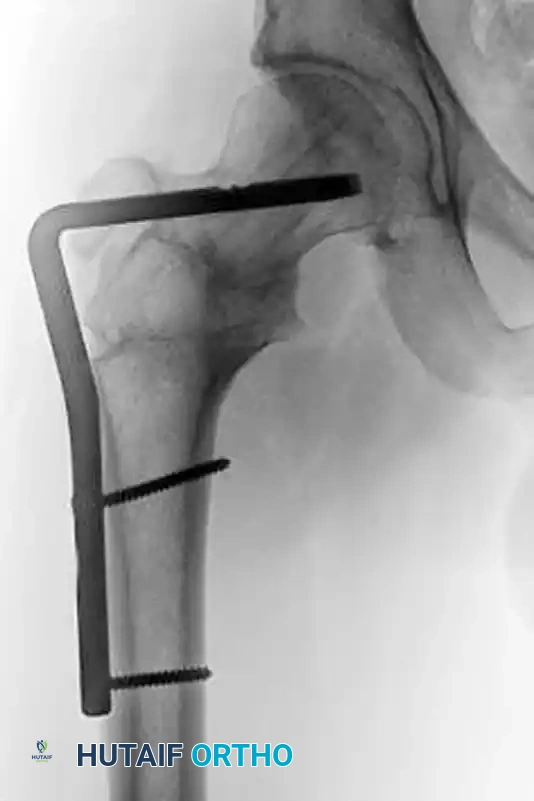

When malreduction is identified early in a physiologically robust patient, revision open reduction and internal fixation (ORIF) may be attempted, often utilizing more rigid constructs such as proximal femoral locking plates to achieve absolute stability.

Figure: Postoperative radiograph following revision ORIF, demonstrating improved alignment.

Figure: Orthogonal view of the revision ORIF utilizing a fixed-angle device to prevent recurrent varus collapse.